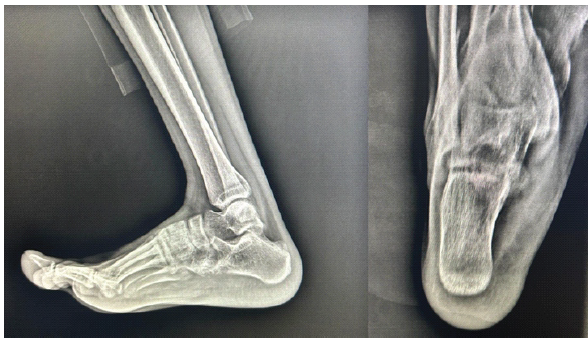

The post-operative recovery was uneventful, with full weight bearing achieved at 4 weeks. At 6 months follow‑up, the patient was asymptomatic with significant functional improvement and showed no recurrence clinically as well as radiologically (Fig. 6).

Figure 6: Post-operative 6 months follow-up plain radiographs showing no signs of recurrence.